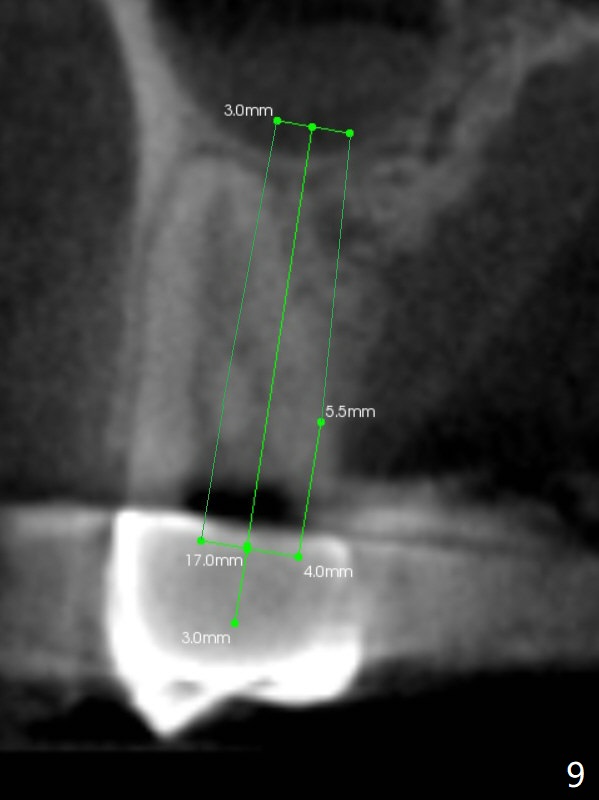

A 64-year-old man requests implant restoration after the upper FPD dislodges (Fig.1). The measurement of the septal height at #2 by PA (Fig.2) is not as precise as CBCT (Fig.11, taken 4 years earlier). There appears to be 2.8 mm bone apical to the tooth #4 (Fig.2); in contrast, the bone is more or less buccal and palatal to the root apex shown by CT (Fig.5). Furthermore CT more clearly shows apical lesions of the tooth #5 (Fig.3,4) than PA (Fig.2). In addition to pulpal test, RCT should be done for #5 prior to implant placement at #4.

After extraction of the tooth #4, osteotomy is initiated in the middle of the palatal slope (Fig.6), followed immediately by change in trajectory (Fig.7). The depth of the osteotomy is ~ 5 mm (Fig.8), followed by 2.8 mm round bur from Sinus Lift Master Kit. Press the burs palatally. Following Vanilla Graft (red circles), place a 3.5 or 4.0x17 mm dummy and final implants (Fig.3,9,10).